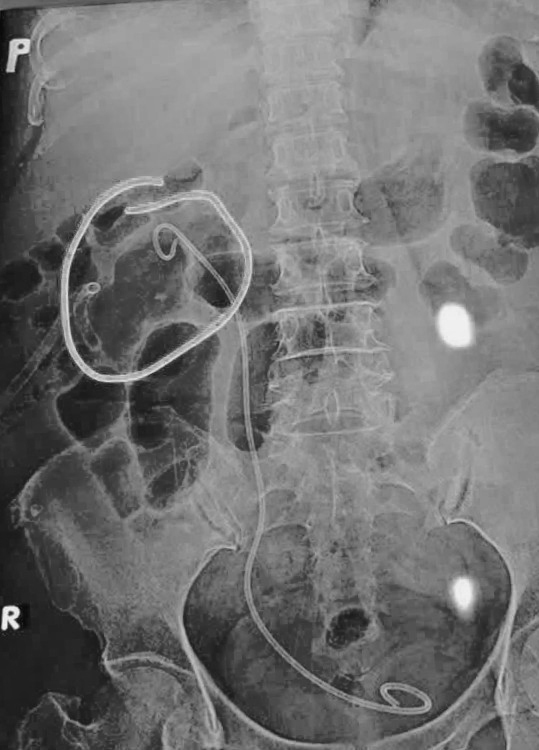

CT scan hệ niệu ghi nhận viên sỏi kích thước khoảng 3x3 cm ở thận phải. (Ảnh: Bệnh viện Hạnh Phúc cung cấp).

Hình chụp X-quang cho thấy khối sỏi đã được tán sạch hoàn toàn. (Ảnh Bệnh viện hạnh Phúc cung cấp)